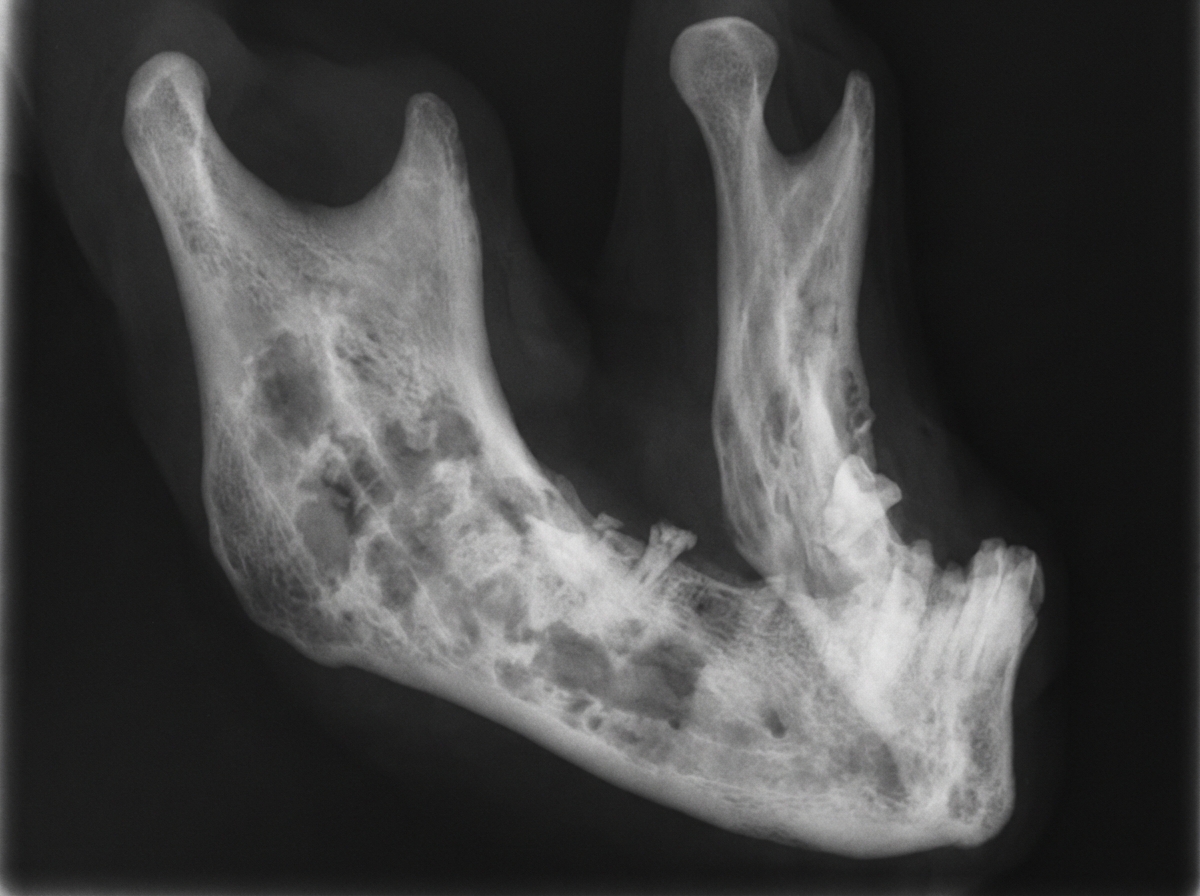

Explanation: ***More destruction of bone*** - Radiotherapy causes **radiation osteitis** and **osteoradionecrosis**, leading to progressive bone destruction and necrosis. - **Impaired vascularization** and cellular damage result in weakened bone structure and increased susceptibility to fractures. *Response to radiotherapy is good* - While radiotherapy may effectively treat tumors, the **bone tissue itself responds poorly** to radiation exposure. - **Bone cells** (osteoblasts and osteocytes) are particularly sensitive to radiation damage, leading to compromised bone integrity. *Fast healing* - Radiation actually **impairs bone healing** by damaging blood vessels and reducing cellular regeneration capacity. - **Delayed union** or **non-union** of fractures is common in irradiated bone due to compromised osteoblastic activity. *Tumor regression is not affected* - While tumor regression may occur with adequate radiation doses, this doesn't address the **direct effects on bone tissue**. - The question specifically asks about bone changes, not tumor response to radiotherapy.

Explanation: **Explanation:** **Radiation caries** is a rampant form of dental decay that occurs as a secondary complication of radiotherapy for head and neck cancers. **Why Salivary Glands is correct:** The primary cause is not the direct effect of radiation on the teeth, but rather the **indirect effect** of irradiation on the **major salivary glands** (especially the parotid). Radiation causes fibrosis and atrophy of the acinar cells, leading to **Xerostomia** (severe dry mouth). Saliva normally acts as a buffer, provides mechanical cleansing, and contains minerals (calcium/phosphate) for remineralization. When salivary flow is reduced, the oral pH drops, and the protective buffering capacity is lost, leading to rapid demineralization and "radiation caries." **Why other options are incorrect:** * **Enamel & Dentin:** While high doses of radiation can theoretically alter the organic matrix of teeth, mature enamel and dentin are highly radioresistant. The decay seen in these patients is primarily due to the altered oral environment (lack of saliva) rather than direct structural damage to the tooth. * **Oral Mucosa:** Irradiation of the mucosa leads to **mucositis**, which causes pain and ulceration. While this may make oral hygiene difficult, it is not the physiological cause of the caries itself. **High-Yield Clinical Pearls for NEET-PG:** * **Characteristic Appearance:** Radiation caries typically starts at the **cervical (neck) region** of the teeth and can lead to the amputation of the crown. * **Threshold:** Salivary glands are highly radiosensitive; permanent xerostomia can occur at doses as low as **20-30 Gy**. * **Prevention:** Patients should undergo dental evaluation *before* starting radiotherapy and use topical fluoride applications during/after treatment. * **Osteoradionecrosis (ORN):** Another complication of radiation, usually affecting the **mandible** due to its decreased vascularity compared to the maxilla.